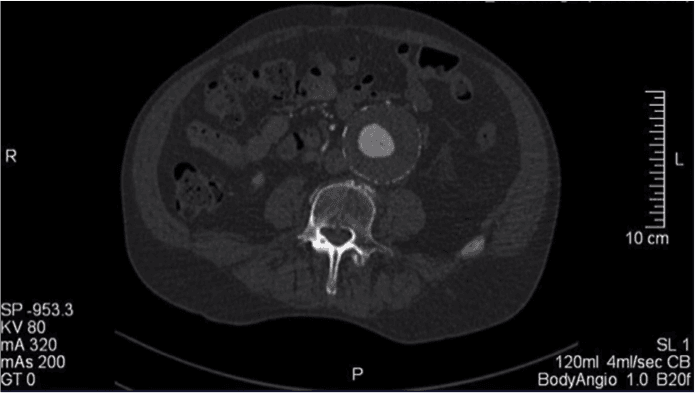

Paciente masculino, 72 anos, com queixa de dor abdominal contínua em mesogástrio há 3 dias refratária a analgésicos convencionais. No exame físico, encontra-se normal hemodinamicamente e presença de m…